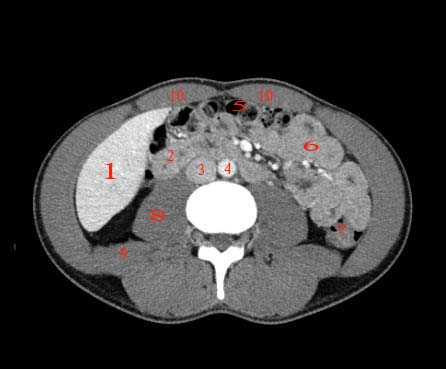

Abdomen axial IQ Test